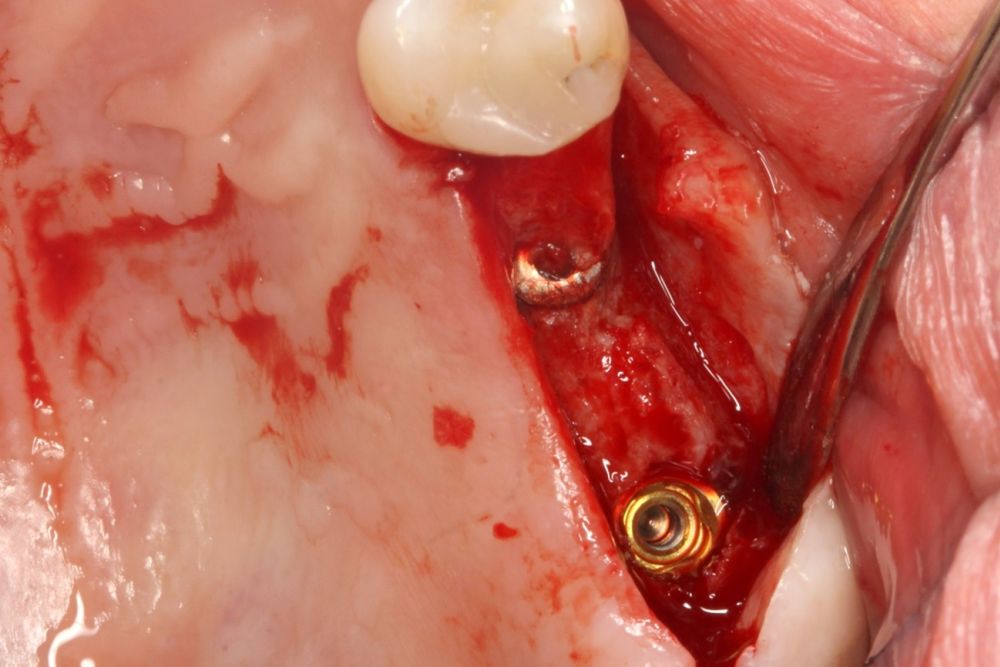

El acceso final a la cortical sinusal se efectuó con una fresa específicamente diseñada para esta técnica (fresa de corte frontal), la cual permite la eliminación controlada del suelo del seno maxilar sin comprometer la integridad de la membrana de Schneider10. Una vez expuesta la membrana a través de la perforación en la cresta ósea, se realizó su elevación de manera controlada, colocándose el injerto consistente en hueso autólogo obtenido del fresado de otras localizaciones en las que se colocan implantes en el mismo acto quirúrgico embebido en PRGF-Endoret. Por último, la colocación del implante se llevó a cabo con un motor quirúrgico calibrado a 25 Ncm y 25 rpm, mientras que la inserción final se realizó manualmente mediante una llave dinamométrica para asegurar una fijación óptima (Figura 1).

Entre cuatro y cinco meses meses después se realiza la carga del implante, en una primera fase con una prótesis provisional de carga progresiva, siempre mediante transepiteliales y, posteriormente la prótesis definitiva entre 1 y 2 meses tras la carga inicial.

En las Figuras 7- 13 se muestra uno de los casos incluidos en el estudio.